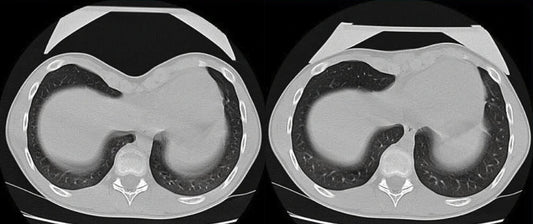

About Vacuum Bell Therapy

The Vacuum Bell is a simple, non-invasive tool used for the non-surgical treatment of Pectus Excavatum. It is currently the leading non-surgical treatment for Pectus Excavatum.